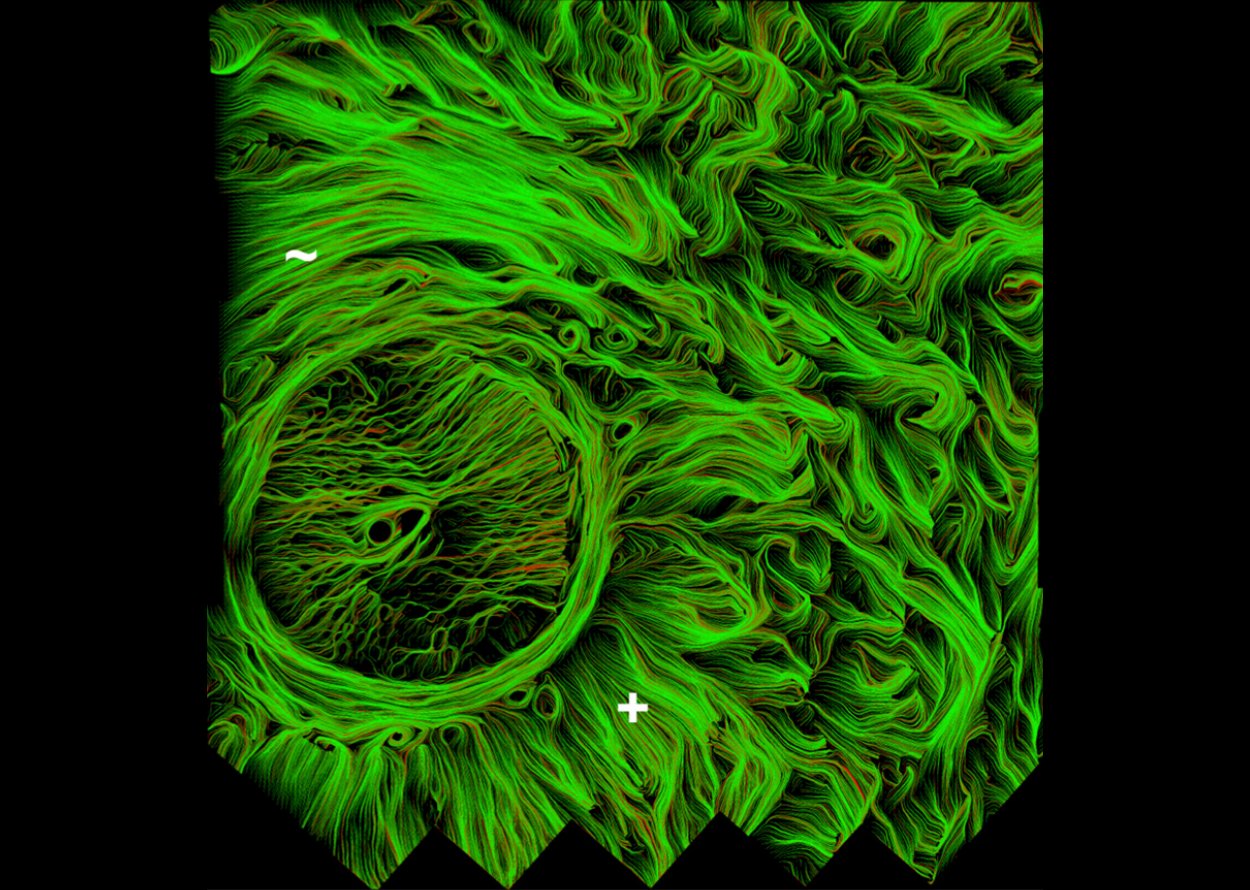

• Real-time imaging of optic nerve head collagen microstructure and biomechanics using instant polarized light microscopy

• PY Lee, B Yang, Y Hua, S Waxman, Z Ziyi, F Ji, IA Sigal

• Experimental eye research, 217, 109867, April 2022.